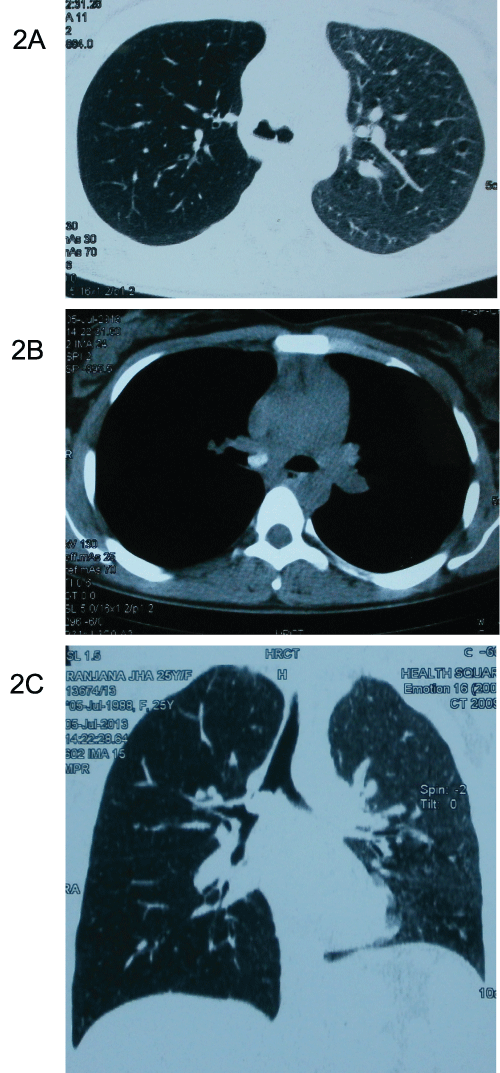

Figure 2: CT scan of the thorax showing a foreign body in the right main

bronchus completely occluding it (2a).Hyper lucent right lung field suggestive

of post obstructive hyperinflation due to ball valve effect is also seen (2b). The

coronal section of the same CT scan shows endobronchial opacity in the right

main bronchus which is almost completely occluding the lumen of the right

main bronchus (2c).

On examination, blood pressure (100/78mmHg), pulse rate (94/min) and respiratory rate (22/min) were normal. Examination of chest revealed no significant abnormality. Other systemic examination was also unremarkable. Posteroanterior radiograph of chest was normal (Figure 1). In view of persistent symptoms, CT scan examination of the thorax was (Figure 2) done. It revealed endobronchial opacity in the right main bronchus suggestive of a foreign body which was almost completely occluding the lumen of the right main bronchus. Hyperlucency of the right lung fields was also observed suggestive of post obstructive hyperinflation. The opacity looked well defined and did not appear to arise from the wall of the bronchus. Patient’s history was reviewed again and she recollected that on the night prior to onset of symptom, she was chewing a betel nut and while laughing on a joke during conversation she had likely aspirated it.